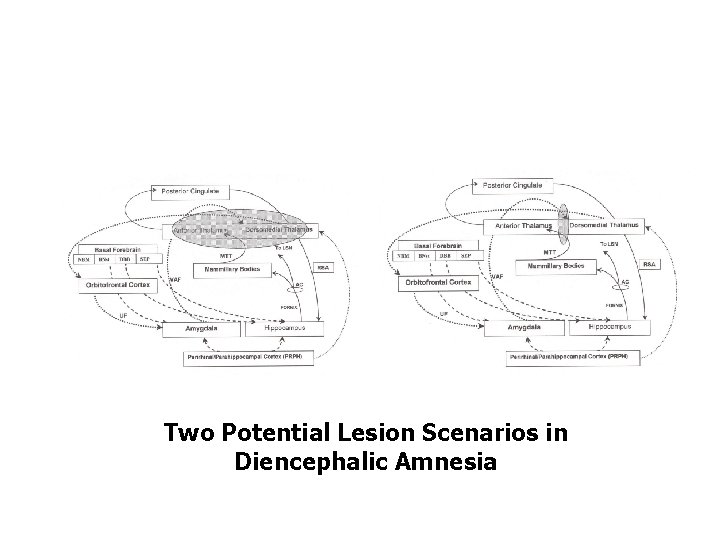

Two Potential Lesion Scenarios in Diencephalic Amnesia